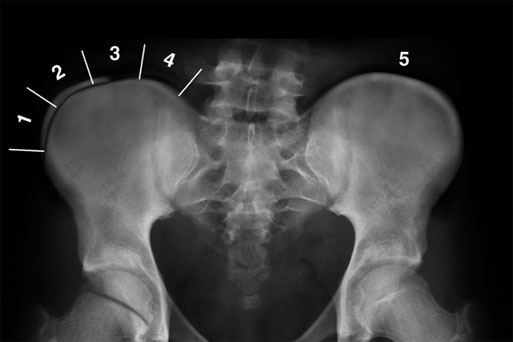

방사선에서도 쉽게 관측할 수 있는 것이 바로 장골골단 입니다.

각 단계마다 확인해보면 1단계는 25% 이하, 2단계는 25~50%, 3단계는 50~75%, 4단계는 75~100% 골화가 진행되는 것으로 분류하고, 5단계는 장골에 유합되는 것입니다.

아래의 그림은 그렇다면 Risser 3 겠지요? 대퇴골두에도 아직 성장판이 남아 있는 것을 알 수 있습니다.